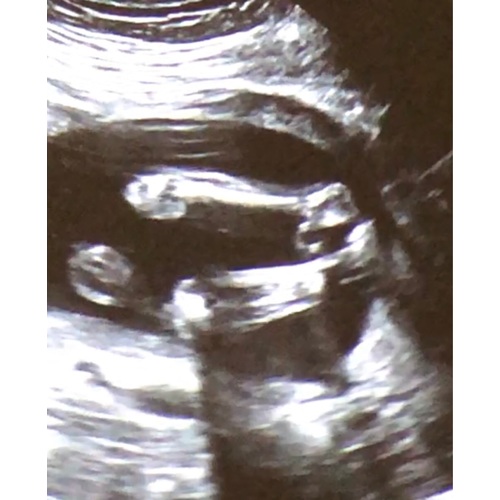

Ik krijg een jongetje. Bij jouw echo is het eerlijk gezegd lastig te zien!

Wauw dit is geen makkelijke. Het geslacht is goed doorbloed op deze foto daarom maakt het het lastig. Ik heb ff wat van internet geplukt ter vergelijking hieronder.

@Amsterdammer, bij precies hoeveel weken is deze echo gemaakt en had je toevallig nog een foto?

20+1. Het is een still van een filmpje dat we hebben gemaakt vanaf het scherm. Andere foto’s met potty shot hebben we helaas niet